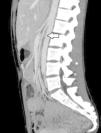

Se practicó una angio-tomografía computarizada, que ya no demostró la presencia de trombosis de la vena cava inferior, pero sí trombosis de la vena renal y la vena ovárica izquierda (figura 1), así como una estenosis de la vena renal izquierda en su paso entre la aorta y la arteria mesentérica superior, compatible con un SCN (figura 2).

Figura 2. Vista sagital. Se observa compresión de la vena renal izquierda entre la aorta y la arteria mesentérica superior.